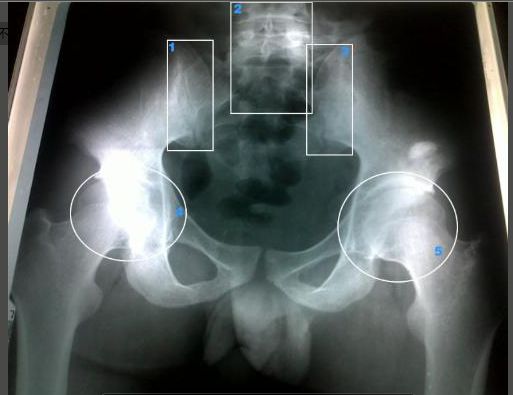

强直性脊柱炎以骶髂关节和脊柱附着点炎症为主要症状的疾病。与HL ...

强直性脊柱炎,是一种原因不明的、以中轴关节慢性炎症为主的全身 ...